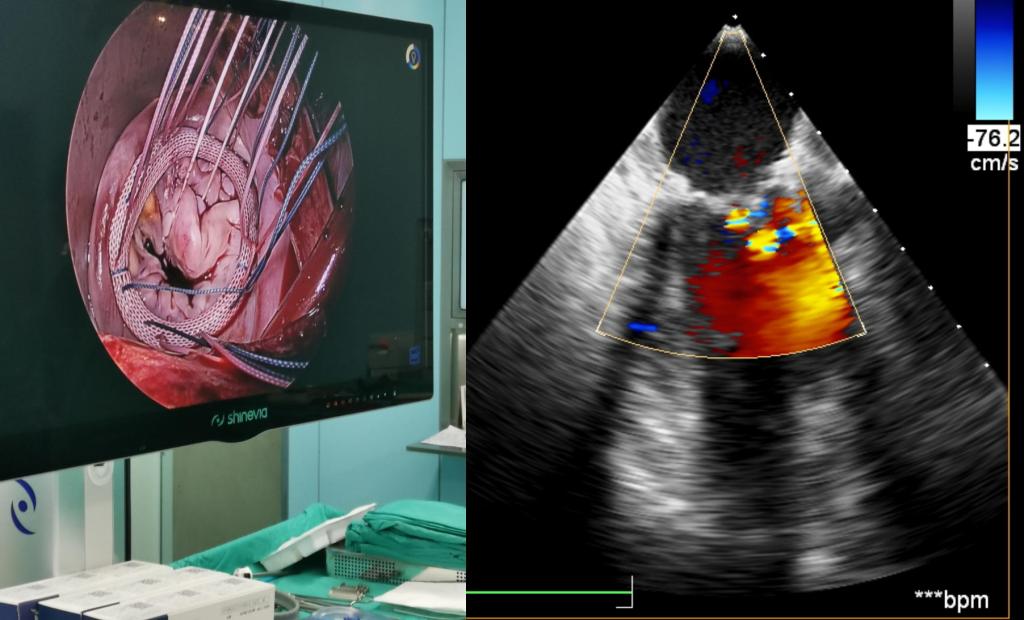

经过积极完善术前检查,心脏超声提示二尖瓣后叶脱垂(P2区),偏心反流(3+—4+级),三尖瓣少量反流,目前最严重的就是二尖瓣这扇“门”,如果不及时处理,患者很快就会出现心衰,甚至危及生命,考虑患者高龄,同时不愿接受人工瓣膜置换,高峰主任团队经过缜密的研究和充分的评估,认为患者有微创手术瓣膜成形的条件,可以通过该术式解决这个大难题。相较于瓣膜置换术,瓣膜成形对主刀医生在术中的精细操作与精准判断提出更高的要求;而微创手术,减少了术中的牵拉和损伤,术后胸骨完整性得以保留,具有创伤小、出血少、恢复快,对术后美观和呼吸功能具有显著优势。在兄弟科室的密切配合下,仅用3个多小时,高峰主任团队通过右侧肋间一个5厘米的小口子,成功对损坏的二尖瓣进行了修复重建,心脏复跳后复查心脏超声,二尖瓣微量返流,手术效果满意。患者安返心外科监护室,在医护人员的精心照护下,患者恢复良好,第二日转回普通病房进一步康复治疗。